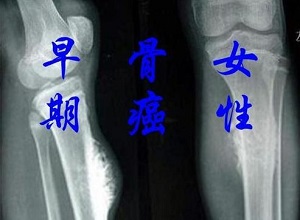

郑州中医肿瘤医师王卫昌介绍:骨癌早期有哪些症状表现?骨癌是一种严重的骨科疾病,死亡率很高,早发现、早治疗是关键。那么骨癌的症状是什么呢?让我们来看看下面的内容。

骨骼是人体的支撑,是人类行动的重要组织。虽然骨骼是身体的重要组成部分,几乎可以在每个x光片上看到骨骼,但很少有骨癌会被意外发现。骨系统与其他器官一样,患有来自任何组织成分的肿瘤或来自其他器官的转移性病变。骨癌的初症状不是很明显,下面一起来了解一下。